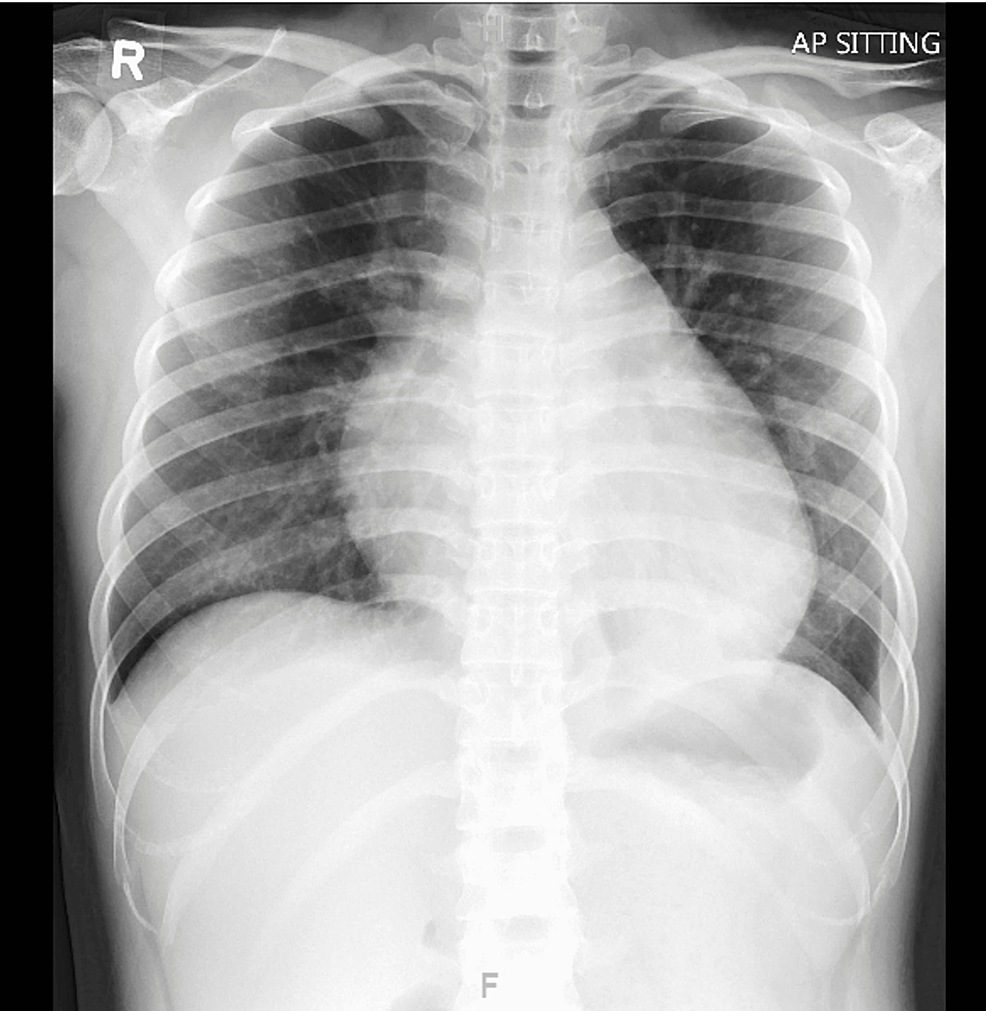

(PDF) A Case of Beriberi in a young patient take advantage of clinical and laboratory clues. Beriberi Usmle Limited storage in body (30mg) stores of thiamine last around 1 month. The heart fails to function, leading to edema and fluid. Thiamine deficiency, or beriberi, refers to a lack of thiamine pyrophosphate, the biologically active form of the vitamin known as thiamine (also spelled thiamin), or vitamin b. Dry beriberi and wet beriberi. Wet beriberi is present when the. Beriberi Usmle.

Figure 1 from Fulminant beriberi heart disease with lactic acidosis presentation of a case with Beriberi Usmle The clinical picture of vitamin b1 deficiency is known as beriberi, of which there are two main types: Limited storage in body (30mg) stores of thiamine last around 1 month. Can be made by measuring increased transketolase activity after. Diagnosis is clinical and difficult to confirm, treatment is simple/inexpensive/effective, there is little risk to treatment, and the risk of morbidity/mortality. Beriberi Usmle.

(PDF) Beriberi A Reversible Cause of Acute Severe Pulmonary Hypertension Beriberi Usmle Can progress slowly or quickly and be fatal. The heart fails to function, leading to edema and fluid. Dry beriberi and wet beriberi. Limited storage in body (30mg) stores of thiamine last around 1 month. Wet beriberi is present when the cardiovascular system is involved. Thiamine deficiency, or beriberi, refers to a lack of thiamine pyrophosphate, the biologically active form. Beriberi Usmle.

Beriberi A Reversible Cause of Acute Severe Pulmonary Hypertension Cureus Beriberi Usmle Diagnosis is clinical and difficult to confirm, treatment is simple/inexpensive/effective, there is little risk to treatment, and the risk of morbidity/mortality from not. Wet beriberi is present when the cardiovascular system is involved. Can be made by measuring increased transketolase activity after. Can progress slowly or quickly and be fatal. The heart fails to function, leading to edema and fluid.. Beriberi Usmle.